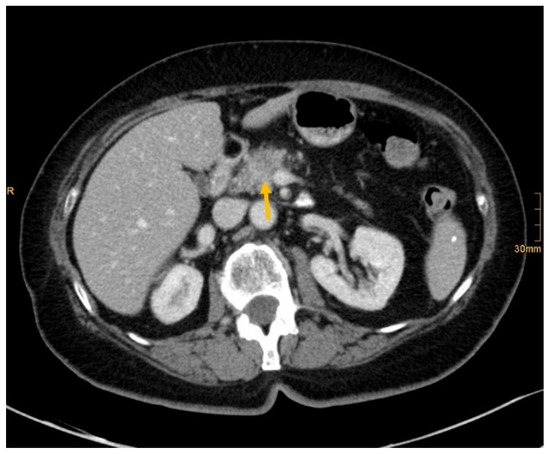

Figure 3. Pancreatic cancer (arrow). All readers identified the lesion in absence and presence of clinical information (Recurrent epigastric pressure and 9 kg weight loss in 4 months.).

There are several reasons why tumors and metastases could be missed by radiologists. Firstly, the interpretation of oncological CT data sets is challenging; often multiple abnormalities are present in a single patient. Lesions may be benign and not always malignant. Therefore, findings could be undercalled and misinterpreted as benign (e.g., Figure 2) [1]. Findings may also be too small to be classified as malignant or may be overlooked (e.g., Figure 4). Additionally, findings, particularly of the lung, could be consistent with a postinflammatory benign aetiology due to configuration and subpleural location (e.g., Figure 5) [46]. Secondly, the so-called satisfaction of search represents another possible influence on the detection rate of malignant lesions. Satisfaction of search represents an interference of a radiological finding with the detection of further abnormalities [1,47]. Radiological image interpretation often follows a fixed procedure. Thus, as soon as a finding (mostly the primary tumor) is made, further lesions as metastases may be missed. This may explain the lower rate of true positive metastatic findings. Further reasons for missed metastatic lesions can be assumed. Metastases are often small, not reliably distinguishable from benign lesions and therefore an unequivocal diagnosis is often impossible without follow-up imaging or complementary procedures such as MRI, hybrid imaging, or biopsy. Moreover, imaging criteria for lymphogenous metastases are often controversial, an accurate identification is challenging. In the past, a short axis diameter of 1 cm was used as the cut-off value for enlarged, malignancy-susceptible lymph nodes [1]. Recent studies suggest different parameters for various anatomic regions, such as 6 mm for retrocrural or 8–10 mm for pelvic lymph nodes. However, enlarged lymph nodes are not always malignant. They also could have an inflammatory aetiology or normal-sized lymph nodes may have tumor involvement [48]. Of course, there are numerous cases in the present study that had been solved correctly. Figure 3 shows an example of a pancreatic carcinoma correctly diagnosed by all three radiologists irrespective of clinical information.